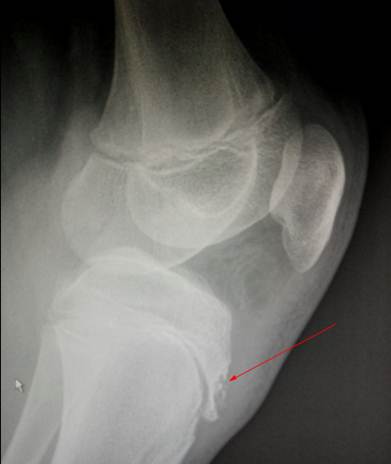

Боковой

снимок коленного сустава мальчика 13 лет. Болезнь Огуста – Шлаттера. Очень хорошо виден очаг поражения эпифиза

большеберцовой кости в зоне её бугристости. Костная ткань в зоне поражения

разрежена и фрагментирована.